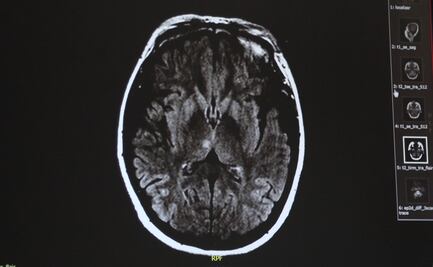

Se cree que los implantes para estimular la memoria estarán disponibles en el mercado dentro de una década. Pero ya hay especialistas preocupados por el riesgo de que puedan ser manipulados con fines maliciosos